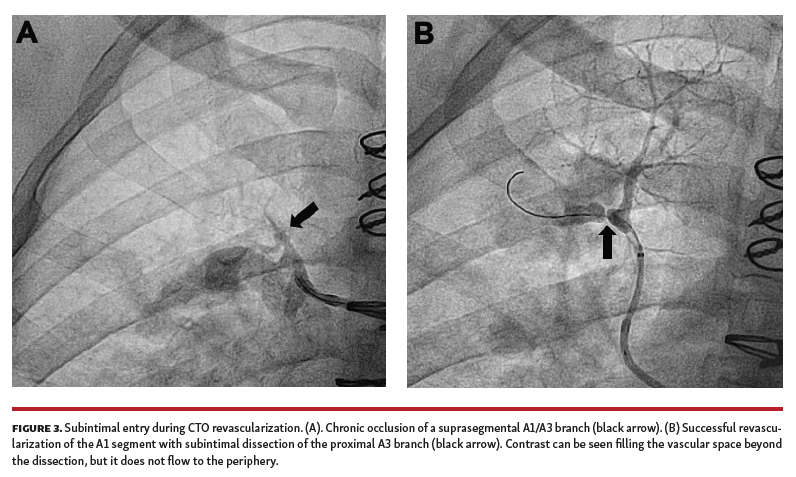

One clear challenge for CTO intervention is interpretation of distal lesion pathology. For example, early interventions occasionally resulted in an angiographic pattern of contrast distal to the lesion within a vascular space, but without distal flow into the capillary bed or pulmonary veins. We initially interpreted this as heavy thrombotic disease beyond the proximal occlusion; however, attempts at distal balloon angioplasty never resulted in restoration of forward flow into the periphery or pulmonary venous return when this initial pattern was seen. It was only after repeated interventions that we recognized this as the angiographic pattern of subintimal dissection within the PAs (Figure 3). As our understanding of subintimal vessel anatomy evolved and our success rate improved, we found that re-entry into the PA lumen just beyond the occlusive cap with either STAR or Stingray balloon technique resulted in significant vessel recruitment. In hindsight, the vast majority of our failed interventions were due to misinterpretation of subintimal dissection as heavy thrombotic burden, offering the possibility for higher success rates during the initial intervention as we improve our ability to work within this space.